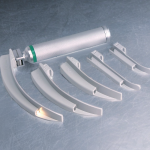

Benötigtest Material zur endotrachealen Intubation

Benötigtest Material zur endotrachealen Intubation

| Laryngoskop |

- (Video) Larnygoskop,

- Laryngoskopeinführung in den rechten Mundwinkel

- Zunge aufladen

- Laryngoskop vorschieben

- Anheben des Zungengrundes

- aufrichten der Epiglottis

- ggf. BURP Manöver